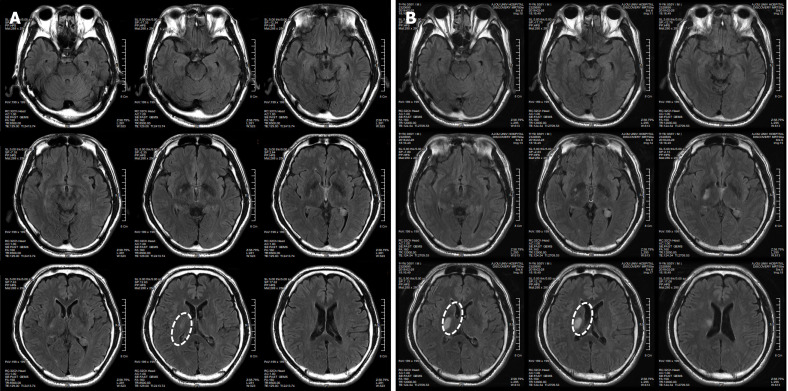

現(xiàn)病史

患者于2018年2月17日至18日出現(xiàn)暫時(shí)性無力癥狀,早上醒來后突發(fā)急性中風(fēng),導(dǎo)致左上肢和下肢癱瘓?;颊咴诖髮W(xué)醫(yī)院急診室被診斷為Rt紋狀體囊性梗死(圖1A)。他于2018年3月2日出院,僅接受了阿司匹林處方,因?yàn)楦鶕?jù)腦計(jì)算機(jī)斷層掃描 (CT) 掃描,他的腦血管正常,盡管他的病情在住院期間惡化(圖1)。出院當(dāng)天,他被送往康復(fù)??漆t(yī)院接受長期康復(fù)治療。然后他于2018年3月13日來韓國首爾生物美容與健康公司 (bBHC)-干細(xì)胞治療與研究所 (STRI)接受干細(xì)胞治療。

圖1:微創(chuàng)人臍帶間充質(zhì)干細(xì)胞移植前患者的腦部計(jì)算機(jī)斷層掃描圖像。

圖1